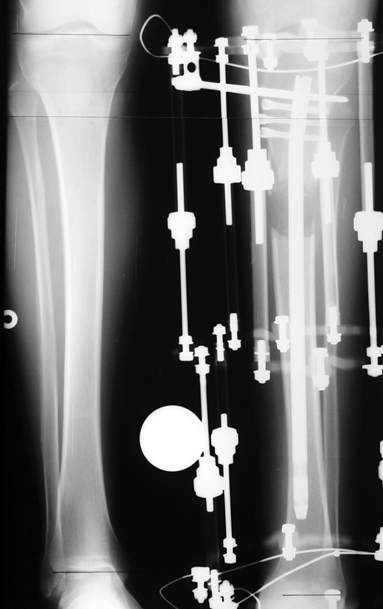

Bu Bacak Kısalık tipi bir kırığın kısalmış pozisyonda kaynaması ile oluşur. Bir çok vaka yetişkinlerde görülür ve sadece bir uzatma ile tedavi edilebilir. Ek deformiteler de aynı anda düzeltilebilir. Bu hastaların çoğu çivi üzerinden uzatma veya tam implante edilen çivi ile tedavi edilebilirler.